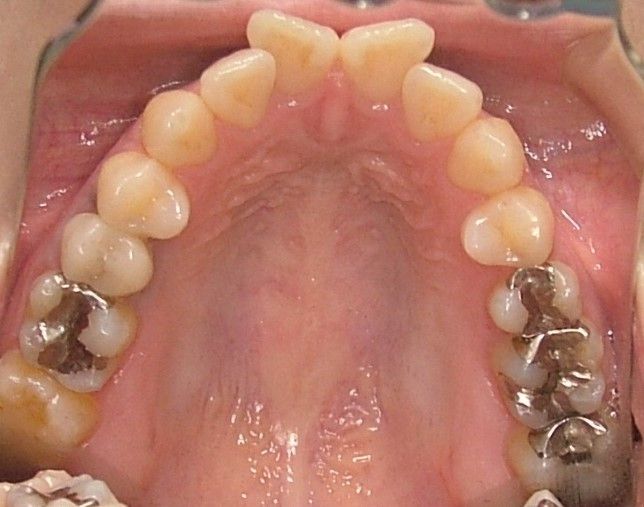

口腔内写真 |

|

| 治療内容 | 掌蹠膿疱症、不定愁訴も治したい。花粉症もあり。ガルバニー電流測定、オリゴスキャン検査、ビタミンDの血中濃度測定 |

|---|---|

| 治療期間・回数 | 5か月・30回 |

| 治療時の費用 | 1,200,000円(メタルフリー代、サプリメント代) ※本症例当時の価格です。最新の費用はこちら |

| リスク・副作用 | 金属除去後に熱が出たそうですが、一時的な好転反応と思われます。このような症状は個人差があるので、特に心配はありません。 |